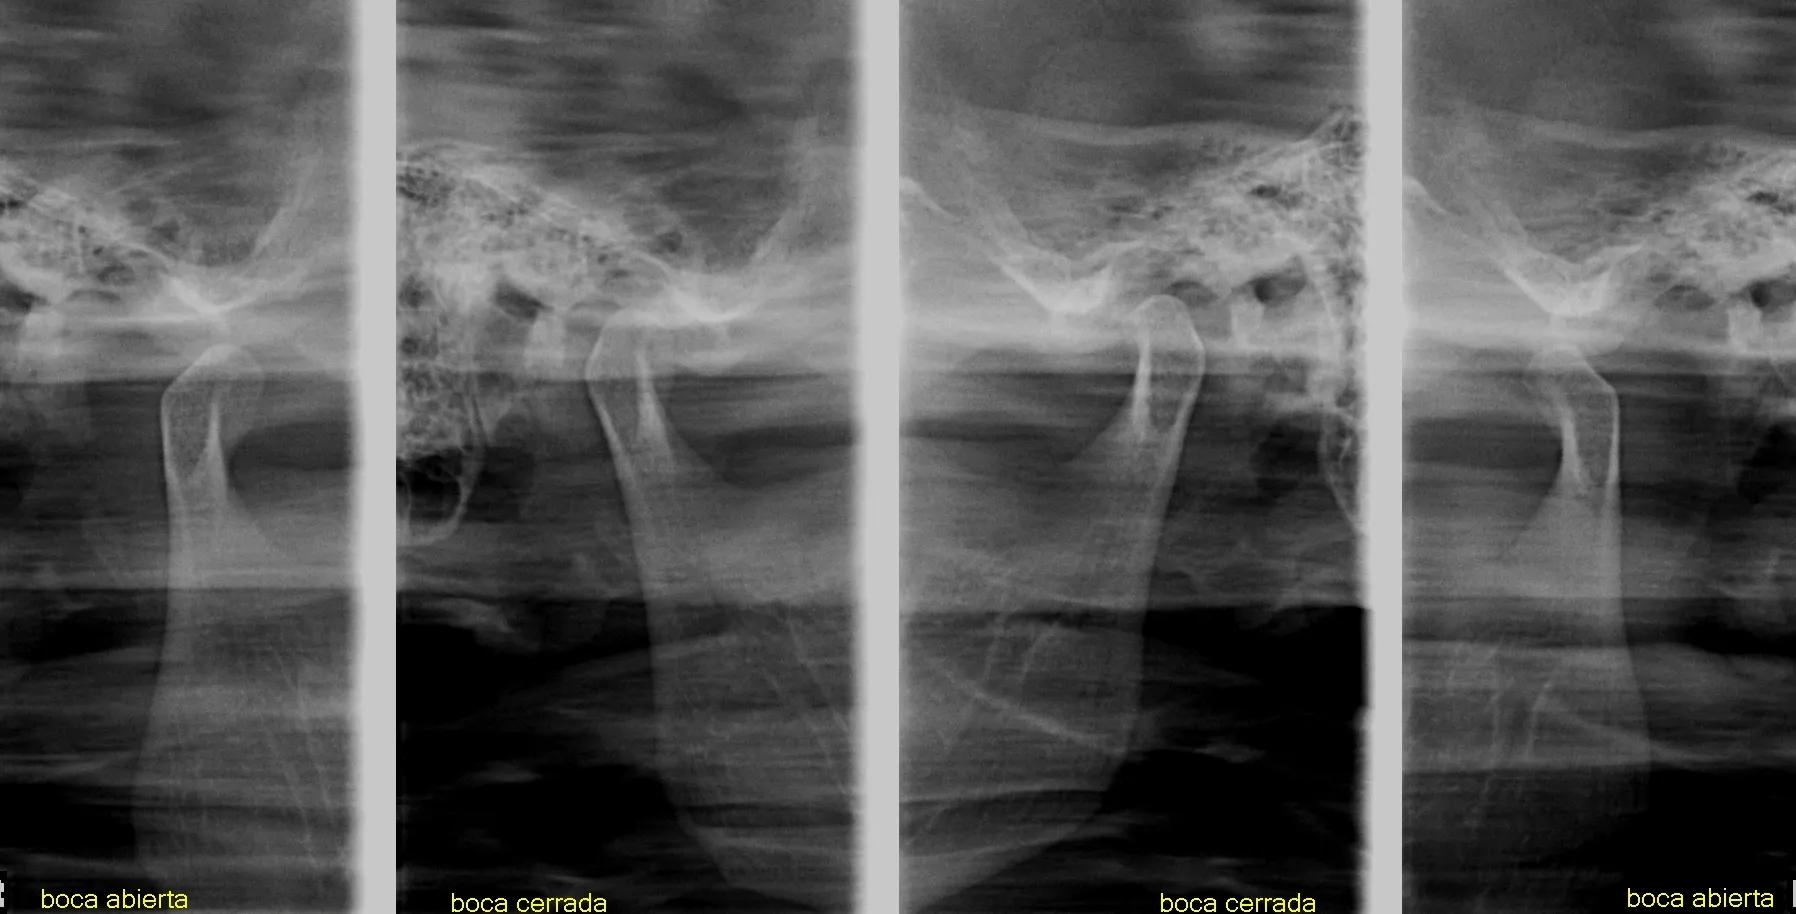

Radiografías Extraorales

Las radiografías extraorales permiten obtener imágenes completas de los maxilares, la articulación temporomandibular (ATM) y las estructuras faciales sin colocar el sensor dentro de la boca.

Realizamos estudios como radiografía panorámica, cefalométrica, de senos paranasales y de ATM, esenciales para tratamientos de ortodoncia, cirugía y diagnóstico integral.